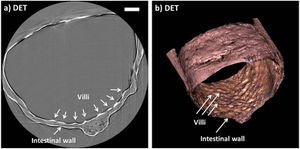

Publication: Sci Rep. 2015 Dec 14;5:18156. PMID: 26657471 | PDF Authors: Hagen CK, Maghsoudlou P, Totonelli G, Diemoz PC, Endrizzi M, Rigon L3, Menk RH, Arfelli F, Dreossi D, Brun E, Coan P, Bravin A, De Coppi P, Olivo A. Institution: University College London, Department of Medical Physics and Biomedical Engineering, London, UK. Background/Purpose: Acellular scaffolds obtained via decellularization are a key instrument in regenerative medicine both per se and to drive the development of future-generation synthetic scaffolds that could become available off-the-shelf. In this framework, imaging is key to the understanding of the scaffolds' internal structure as well as their interaction with cells and other organs, including ideally post-implantation. Scaffolds of a wide range of intricate organs (esophagus, lung, liver and small intestine) were imaged with x-ray phase contrast computed tomography (PC-CT). Image quality was sufficiently high to visualize scaffold microarchitecture and to detect major anatomical features, such as the esophageal mucosal-submucosal separation, pulmonary alveoli and intestinal villi. These results are a long-sought step for the field of regenerative medicine; until now, histology and scanning electron microscopy have been the gold standard to study the scaffold structure. However, they are both destructive: hence, they are not suitable for imaging scaffolds prior to transplantation, and have no prospect for post-transplantation use. PC-CT, on the other hand, is non-destructive, 3D and fully quantitative. Importantly, not only do we demonstrate achievement of high image quality at two different synchrotron facilities, but also with commercial x-ray equipment, which makes the method available to any research laboratory. Funding:

Images acquired with synchrotron-based PC-CT showing a rat small intestine that was decellularized via DET: (a) transverse cross section, (b) three-dimensional view. All scale bars represent 500 μm. Images were processed using the ESRF in-house software PyHST, and analyzed and displayed with ImageJ31 and 3D Slicer. |